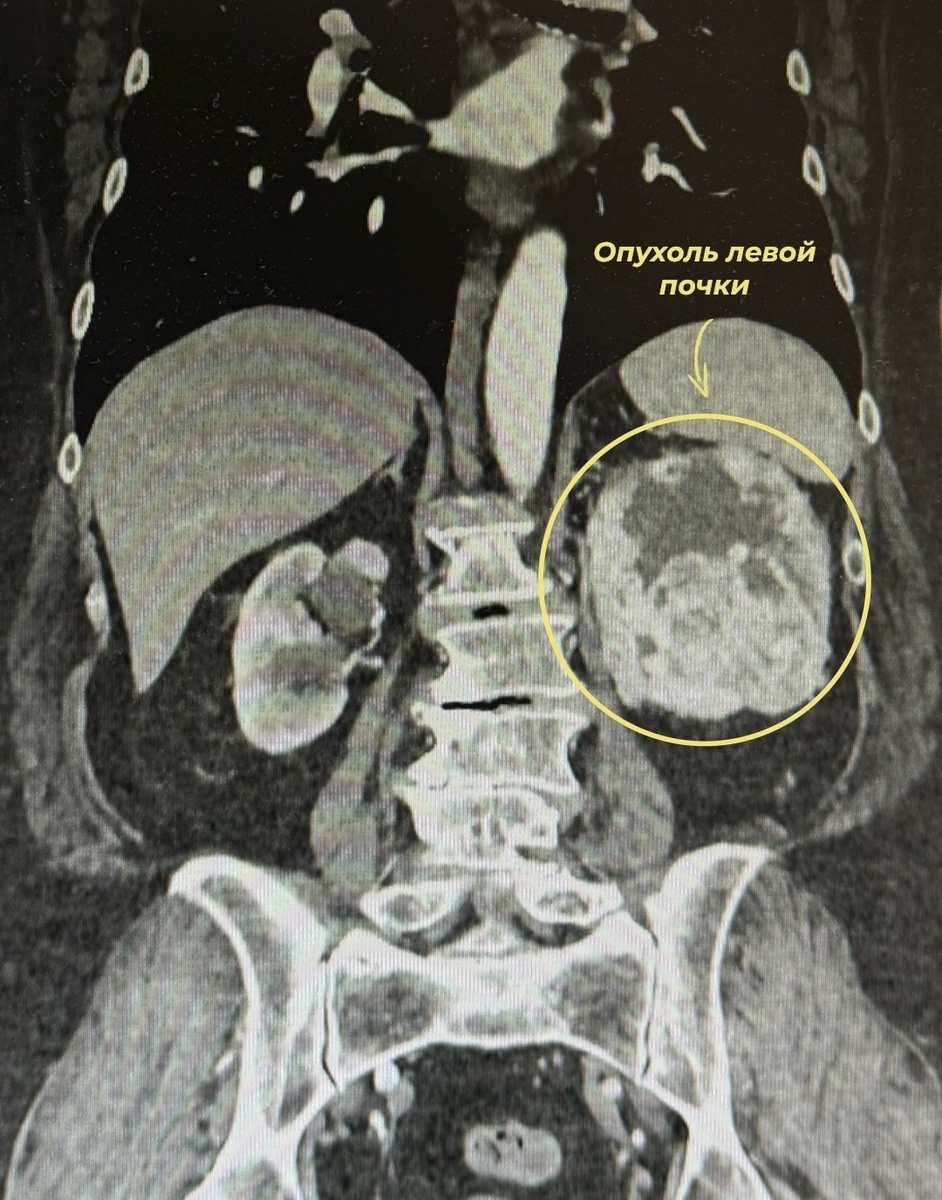

С самого начала рак никак себя не проявлял – женщина пришла к врачам уже когда появились тянущие боли в пояснице и кровь в моче. На МСКТ врачи обнаружили злокачественное новообразование левой почки, оцененное по системе R.E.N.A.L. в 10 баллов.

Опухоль по шкале оценки разрослась на 10 баллов из 10-ти. Фото: Ивановский онкодиспансер